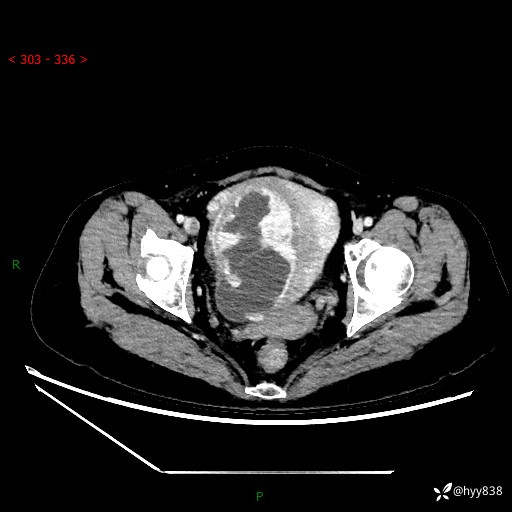

辅助检查:CT

盆腔CT平扫

增强(动脉期+静脉期)